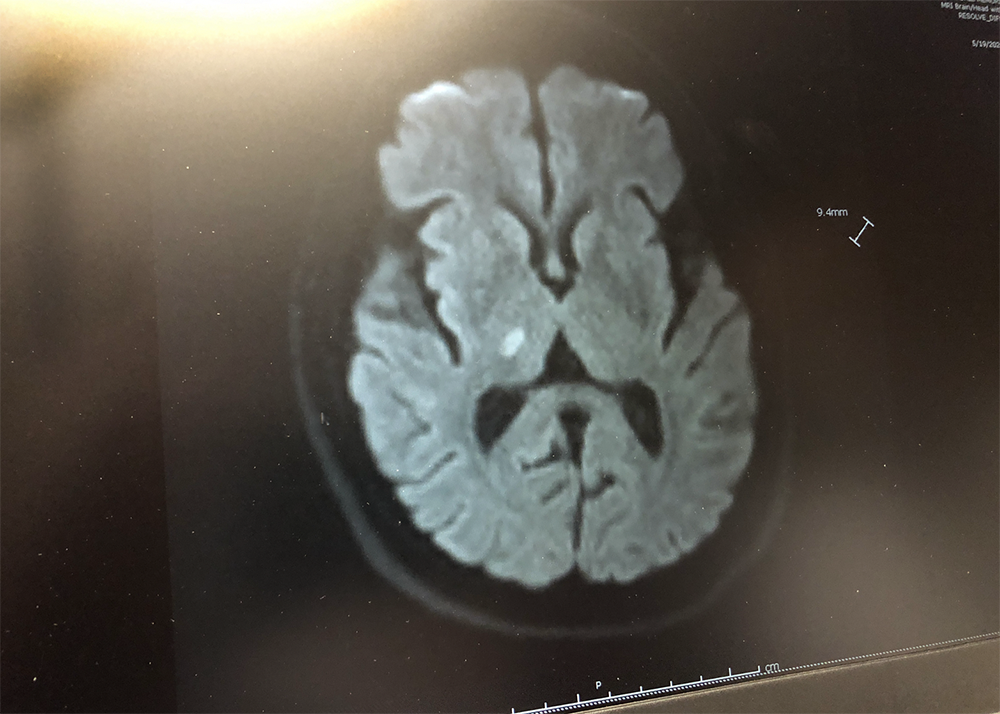

Soon I was moved to my hospital room as an inpatient. The rest of Monday-Wednesday consisted of a battery of tests including CT scans, MRI’s, and whatnot. A number of months later my neurologist, Dr. Alan J. Schmitt, showed me a scan from one of the MRI images and where the problem area was in my brain. The picture below is that scan. In this particular scan, the MRI had taken an image deep within my brain. To better understand the scan, imagine that I was standing up with a digital camera pointing downward above my head. Now imagine that the camera begins to move in a downward motion, moving slowly and actually entering my head until it gets to the bottom of my forehead area—then stops and snaps a picture at that depth. That’s what the scan shows— A slice of my brain somewhere about 4 inches down inside my brain.

The white area in the center of the picture above is the dead brain area that caused my deficits. Doesn’t really look like all that much, does, it? However, the stroke resulted in my brain becoming chronically confused. It now sends pain messages to my left side, mainly to my arm and hand. The pain messages are constant and chronic. 24/7. It appears that my condition will not change going forward and I will have to live with “how I am now.” The last resort would be brain surgery where an electrical implant would be affixed to the inside of my brain somewhere to stop the pain signals from occurring. No thanks.

First let me say that I am very cognizant of the fact that I was very fortunate that my deficits were not worse than they are. Many, people have seriously debilitating strokes that severely reduced their quality of life. Because of that, many stroke victims are at high risk of becoming suicidal. Compared with the brain scan above, their brains show up as almost totally white, with large patches of white, damaged brain areas.